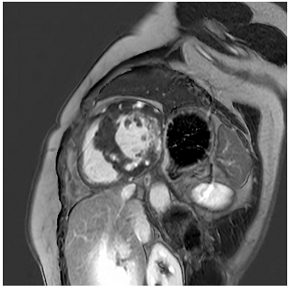

20. Extracardiac Imaging for Identification of Secondary Hypertension and Sequelae of Long-Standing Hypertension

Secondary hypertension affects approximately 5–10% of the general hypertensive population [77]. Imaging may play an important role in the detection and subsequent treatment of both endocrine (such as hyperaldosteronism, phaeochromocytoma, or hyperparathyroidism) and non-endocrine secondary hypertension [78].

The most common cause of primary hyperaldosteronism is an aldosterone-producing adrenal adenoma. Adrenal adenomas usually present as round or oval masses. Using a threshold value of ≤10 Hounsfield units (HU) at non-contrast CT leads to high sensitivity and specificity in their detection [79]. Given their fatty content, adrenal adenomas may also be detected using chemical shift imaging with characteristic signal drop-outs on in- and opposed-phase imaging [80].

Phaeochromocytomas are a rare cause of secondary hypertension and account for only <5% of patients with secondary hypertension. These tumours usually present as large, heterogeneous masses with both necrosis and cystic changes and avid contrast enhancement [81].

Common non-endocrine causes are aortic coarctation (Table 4N) and renovascular hypertension caused by diseases such as fibromuscular dysplasia (FMD) or renal artery stenosis.